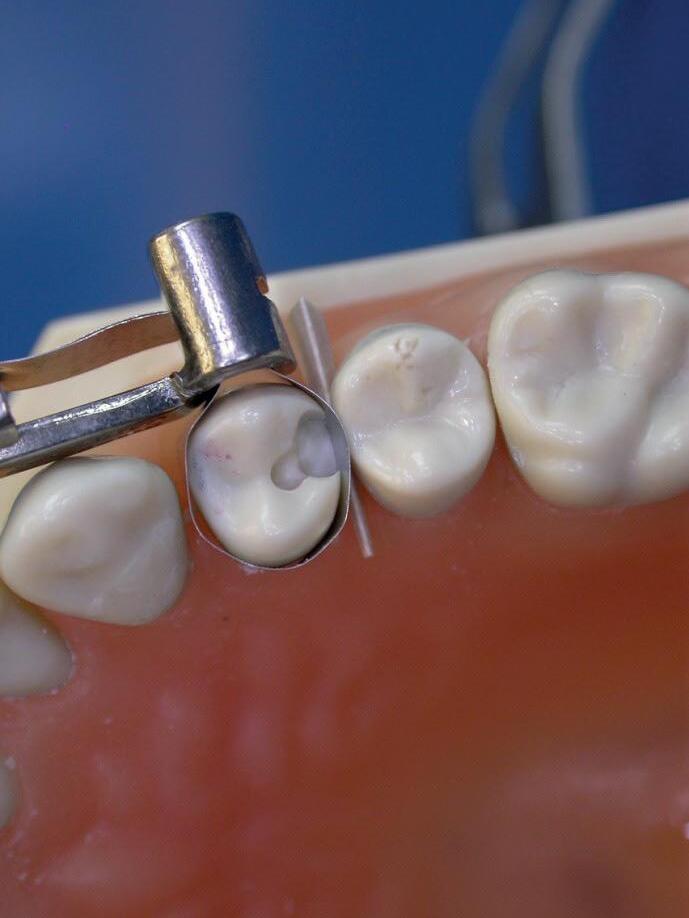

Het vervaardigen van composietrestauraties in de zijdelingse delen is een behandeling die we in de tandartspraktijk dagelijks uitvoeren. Maar hoe zorg je er nou voor dat deze restauratie duurzaam is en dus zo lang mogelijk meegaat? Welke invloed heeft de restauratie op de rest van de dentitie en hoe zorg je voor een voorspelbare vorm, functie en esthetiek?

Stap voor stap word je meegenomen in het proces en leer je werken volgens een vast protocol om het gewenste resultaat te bereiken. Onder begeleiding van onze vaste docent Rixt van Noort krijg je veel praktische tips tijdens deze hands-on cursus, die je meteen kunt toepassen in de praktijk.

De volgende onderwerpen komen aan bod:

• Het gebruik van rubberdam

• De preparatie wordt nader uitgelicht

• De mal en stempel techniek nader bekeken.

• Vorm en oppervlakte structuur in relatie tot de afwerking

• Anatomie

• Functie

• Duurzaamheid

• De materialen en het instrumentarium

Leerdoelen

De cursist:

• Kan eenvoudig en efficiënt een rubberdam plaatsen

• Kent de verschillende preparaties voor composiet

• Kent adhesieve systemen

• Kent de verschillende matrix systemen

• Heeft kennis van vultechnieken

• Heeft kennis van het optimale contactpunt

• Heeft kennis van de occlusale morfologie